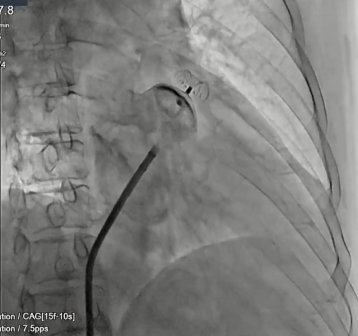

林教授选用型号为LT-LAA-1832、独特小伞大盘设计的LAmbre™左心耳封堵器对患者实施封堵。手术全程未使用食道超声,未对患者进行全麻,一次性封堵完全。释放后牵拉试验,固定盘稳定。再次造影显示封堵后无残余分流,手术仅用25分钟。

(图:术后造影显示封堵后无残余分流)